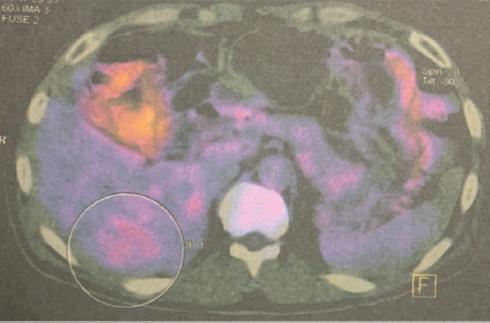

También se lleva a cabo un centellograma con octreotida-Tc-99m que muestra una lesión hipercaptante en el lóbulo derecho del hígado (Fig. 3). No se encuentran áreas anormales en el resto del cuerpo entero rastreado. Se complementa el protocolo con tomografía computada por emisión de positrones (PET) de cuerpo entero, encontrando una lesión hepática en el segmento VI-VII, hipodensa, con aumento de metabolismo (Fig. 4), y aumento difuso de metabolismo en el esófago y el cuerpo gástrico.

Figura 4 Tomografía por emisión de positrones. Se observa un aumento del metabolismo en la lesión localizada en el lóbulo hepático derecho.

En algunos trabajos se ha reportado que la gammagrafía/centellografía resulta ser más sensible que cualquier otro método de imagen para la identificación de un gastrinoma10. Localiza los NET de manera exitosa hasta en un 78-86% y se ha convertido en el estudio de imagen de elección para los pacientes con sospecha de gastrinoma7. Por otra parte, la PET ha revolucionado en los últimos años los protocolos de estudio para buscar neoplasias, gracias a su capacidad de visualizar actividad metabólica. Ambos estudios fueron aplicados en este paciente y sus resultados corroboraron que se trataba de un NET hepático primario, descartando de manera contundente una posible lesión secundaria en otro órgano. Posterior a la realización de pruebas séricas y al encontrar unos valores de gastrina extremadamente altos, se concluyó el diagnóstico de gastrinoma hepático primario.